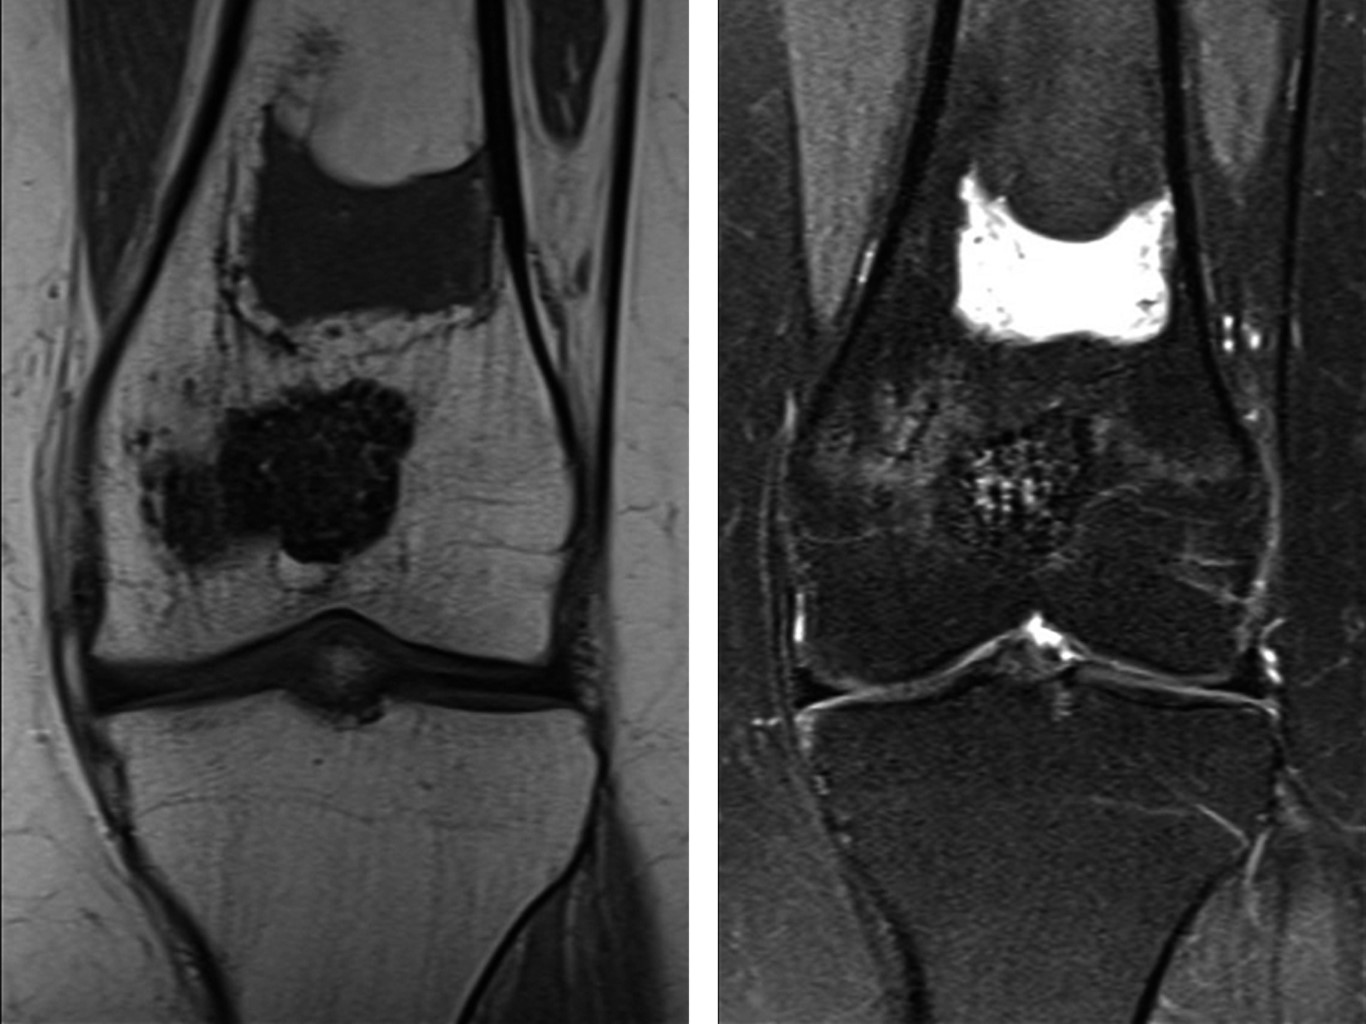

Se realizó el estudio complementario con TAC y RMN; en el cual la TAC de rodilla indicó una imagen lítica metafisaria de fémur distal de bordes circunscritos bien definidos con fractura en hueso patológico, sin colapso de la columna medial (Figura 2) y en la RMN en el corte T2 y supresión grasa, se observó una lesión de márgenes escleróticos sin signos de reacción perióstica, con relleno de aparente densidad líquida levemente heterogéneo, con aparente invasión fisaria, sin compromiso de partes blandas, siendo compatible con neoplasia de origen condral coincidiendo con la sospecha diagnóstica de condroblastoma de fémur distal (Figura 3).

Figura 2

Figura 3